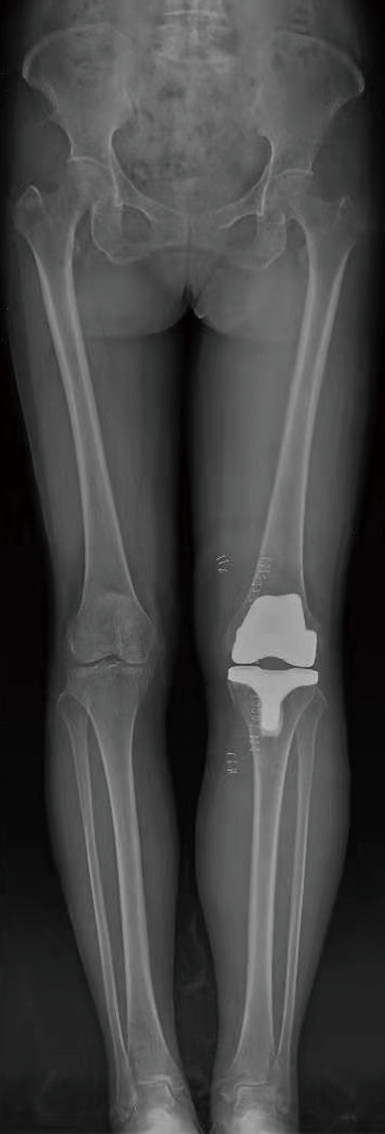

病例4 :使用计算机导航系统对骨性关节炎患者进行全膝关节置换,在术中实时观察假体安装的位置和角度,术后膝关节平衡、稳定,下肢力线得到精准恢复